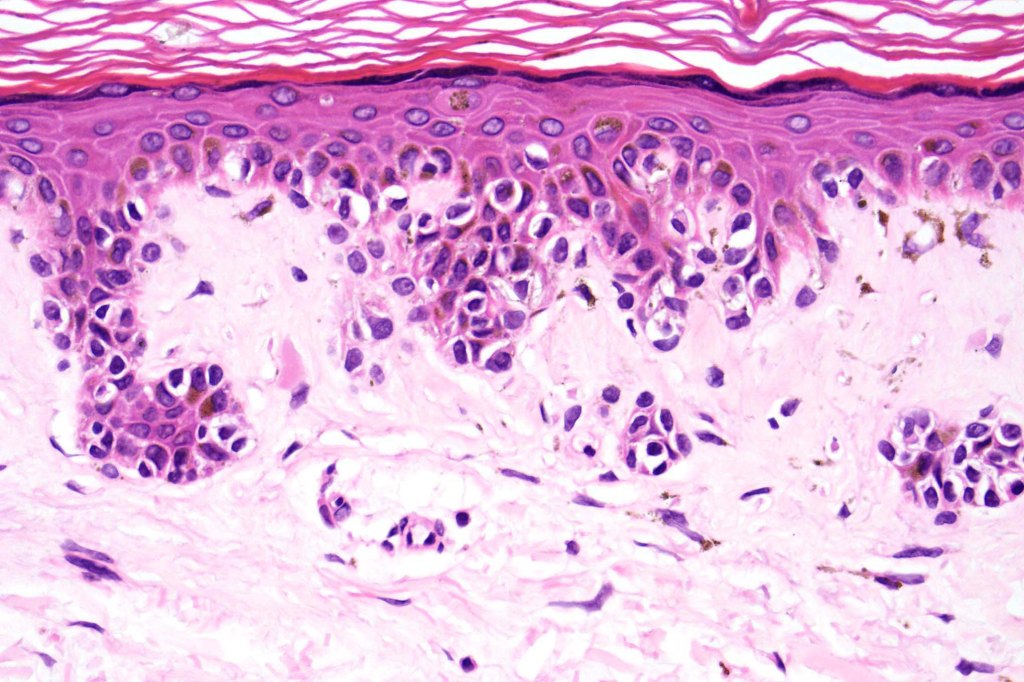

Histological features

- A broad lentiginous proliferation of atypical melanocytes unasscoiated with any loss of the rete ridges

2. Melanocytes generally small, epithelioid (rather than spindled) with either vesicular nuclei and prominent nucleoli or are hyperchromatic.

3. The cells can be present singly, in short pallisades or can extend along a large section of epidermis

4. Pagetoid spread is sometimes seen in more established lesions

7. Fibroplasia not seen and elastosis is either mild or absent

8. An invasive component may be present